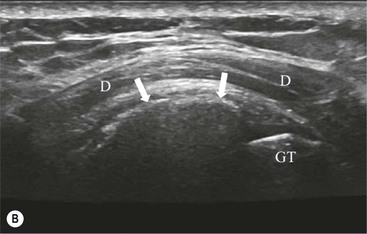

Calcific tendinopathy can be visualised on radiographs as discrete amorphous deposits of calcium density. On US they are echogenic and may or may not cast acoustic shadowing (Fig. 46-8). Small deposits of calcium may be difficult to detect on MRI as both the calcification and surrounding tendon are of low SI.